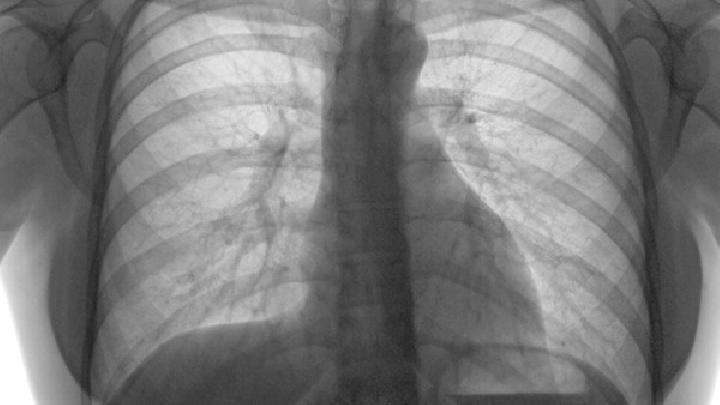

肺癌早期能治好吗?很多人对肺癌存在心理恐惧,一查出患有肺癌就会担心不已。其实早期肺癌并不可怕,只要及早发现,及早选择适合的治疗方法,很多早期肺癌是可以治愈的。但是很多肺癌患者都是错过了最佳的治疗时间,甚至到晚期才治疗,所以治疗无效的患者都是晚期肺癌。专家提醒,肺癌最关键是要早发现早治疗,能抓住早期就成功了一大半,同时在治疗中要保持良好的心态。

肺癌早期能治好吗?这主要取决于是否及时采取了恰当的治疗手段。一般来说,早期肺癌癌肿较小,未发生扩散转移,其最为有效的治疗手段为根治性手术切除,早期肺癌切除后的5年生存率可达60%90%。早期肺癌根治术,不仅要求术者肉眼下达到根治,更重要的是淋巴结完全清除和支气管残端在显微镜下也无癌细胞残留。

肺癌早期能治好吗?肺癌早期的治疗要综合运用多种方法,能迅速消除肿瘤原发病灶引起的各种症状,减轻瘤负荷引起的并发症。生物治疗可以可以提高患者免疫能力,恢复机体的免疫机能,并效防止因局部切除不彻底而引起的复发和远处转移。化疗可以快速杀灭残留的微小肿瘤病灶和体内癌细胞,与生物治疗相配合,全面治疗效果更全面,缩短治疗疗程。早期肺癌的综合治疗可以明显降低后期并发症和复发的出现,提高远期生存率,从而达到治愈的目的。